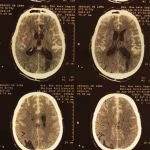

- Traumatismo craniano

- Hematoma cerebral

- Hematoma subdural crônico

- Hematoma extradural

- Contusão cerebral traumática